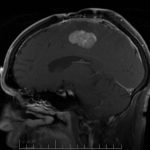

Smoking kills—and this is not an understatement. When you smoke, you put your health and body at risk to countless of diseases and other complications. One of them is oral cancer—which is the number one disease most likely to affect cigarette smokers. Mouth cancer has a 50% death rate, and this percentage hasn’t changed over the past decade.

90% of patients that have oral cancer are smokers. This puts a smoker six times more at risk of contracting the disease as compared to non-smokers. Smoking cigarettes for a long time puts you even more at risk—so the chances of you developing the disease just got higher if you started smoking at a very early age.